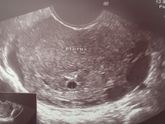

В общем сходила на УЗИ, посмотреть обвитие, и ура, его нет))) Размотался. Ходить все тяжелее, ну еще бы с таким весом то☝️ Включаю режим ждуна. Надеюсь не рожу на нашу годовщину свадьбы — 11 сентября) Хочется все таки отдельные праздники)